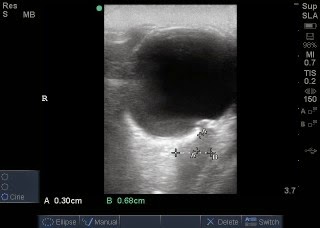

Studies have shown that the first sign of increased intracranial pressure is seen in dilation of the optic disk.[1] As intracranial pressure increases, the CSF can push against the nerve enough to dilate its sheath.[1] The ultrasound will measure the width of this optic nerve sheath, with greater than 5mm (some sources say 6mm) signifying an abnormal result.[2,3] The ultrasound is performed in a supine patient, using a 7.5MHz linear probe over their eyelid. The optic nerve sheath will be the black stripe running down the posterior aspect of the globe.[2] It should be running down the center of the monitor if you have correct placement. You simply measure 3mm down the posterior aspect of the eye, then across that area of the sheath.[2] Measurements should be taken in both eyes, due to the possibility of unilateral papilledema.[1] Once again, a measurement over 5mm correlates with elevated intracranial pressure. An excellent website to visit for a detailed explanation and photos is http://www.sonoguide.com/smparts_ocular.html.[4]

This is an ultrasound image of the normal eye showing the small black stripe posterior to the globe (bottom of image), which is the optic nerve.

Optic Nerve Sheath Diameter (ONSD) measured: Example of measuring the optic nerve sheath. A is the initial measurement going down the length of the nerve, 3mm. B is the width of the nerve sheath, 4.1mm (normal).